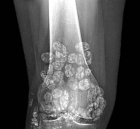

26 year old female with ten year history of right knee pain with intermittent swelling